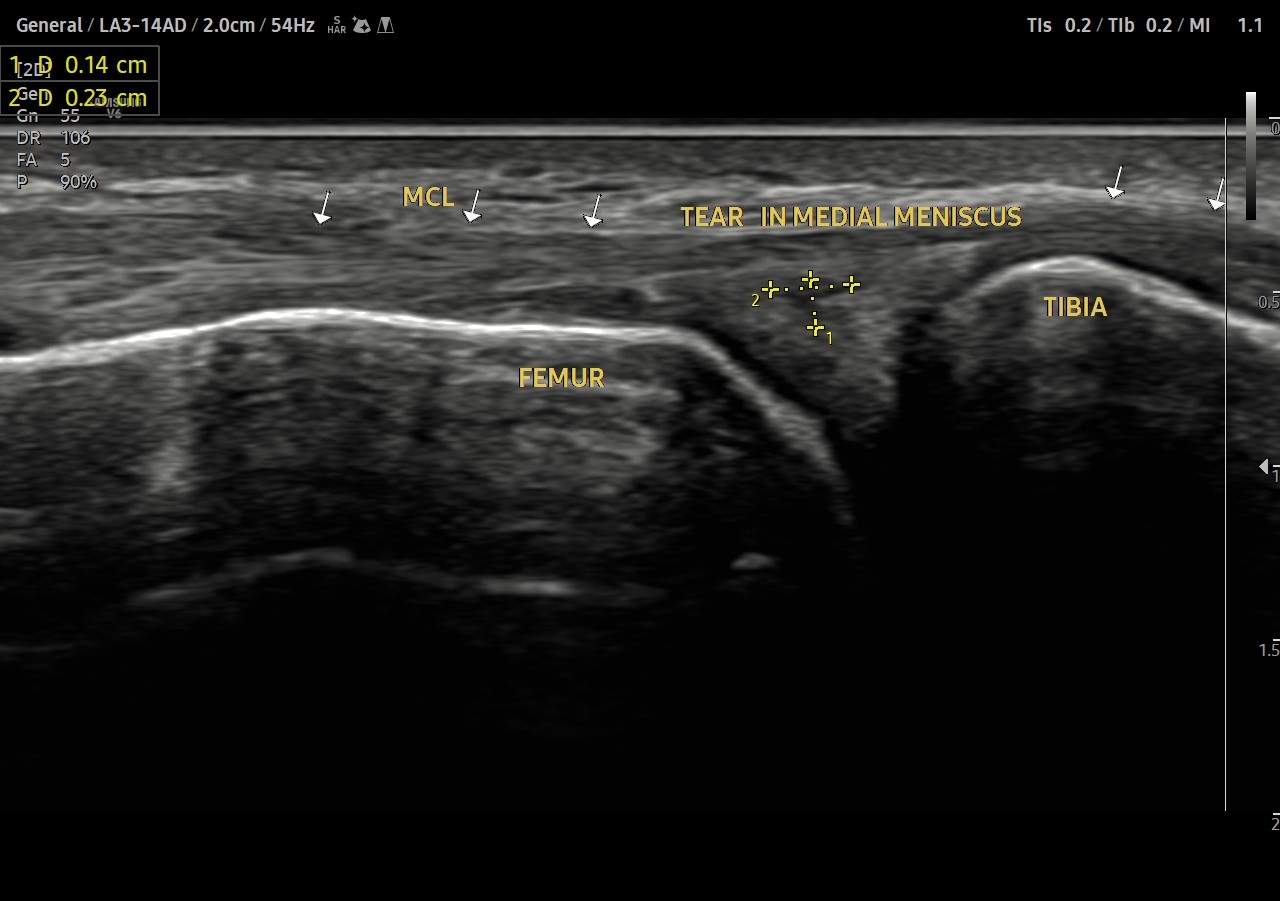

Meniscal tearusg

Anechoic tear in the Peripheral third of posterior body of medial meniscus